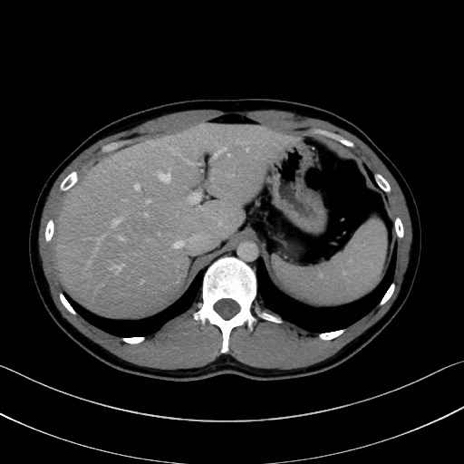

脾静脈の画像解剖

■起始:脾門で脾静脈枝が合流して本幹を形成。

■走行:膵体尾部の後面溝を右走し、膵頸部の後方で上腸間膜静脈(SMV)と合流して門脈を形成。

■主な流入枝:短胃静脈・左胃大網静脈・膵静脈、そして下腸間膜静脈(IMV)(変異あり)。